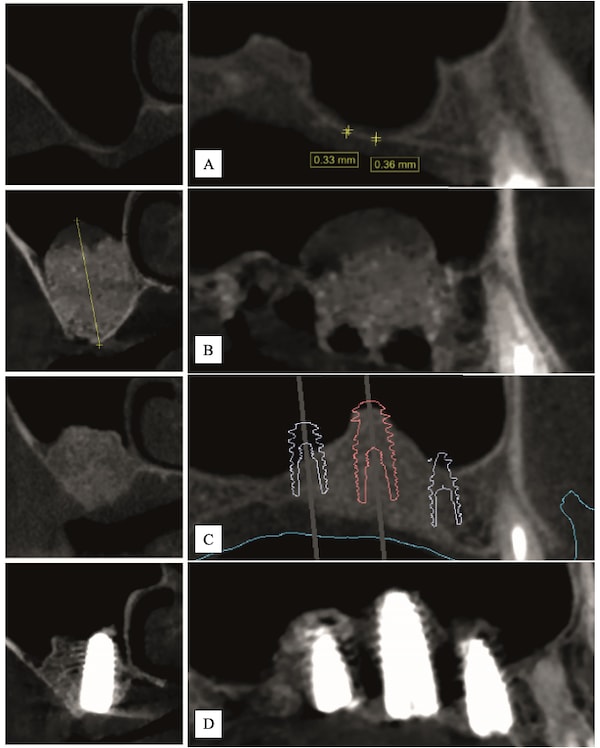

In the posterior maxilla, bone volume, height, and density are often insufficient for implant placement and rehabilitation, which can affect implant long-term stability and success. These anatomical limitations may dictate the need for sinus grafting procedures. Osseodensification is an implant site instrumentation method that enhances bone density and can also be used for transcrestal maxillary sinus augmentation. This technique utilizes bone plasticity through specially designed burs that compact and densify bone along the osteotomy walls while simultaneously propelling bone particles laterally and apically. This process generates a hydrodynamic compaction wave at the bur tip, which propels irrigation fluid into the sinus cavity lifting the membrane and simultaneously compacting bone particles grafting the sinus with autogenous bone. Additionally, the flutes of the osseodensification bur permit the operator to subsequently graft biomaterial, facilitating further elevation of the Schneiderian membrane. Current literature outlines three specific protocols for sinus floor elevation and implant placement utilizing osseodensification with residual bone height (RBH) requirements: ≥6 mm for protocol I, ≥4–5 mm for protocol II, or ≥2–3 mm for protocol III, with concurrent implant placement in the presence of adequate bone and soft-tissue volume. Osseodensification-mediated sinus grafting allows for shorter surgery duration, reduced postoperative edema, less reported pain, and subsequently decreased analgesic intake compared to lateral window techniques. This article details the step-by-step osseodensification sinus lift protocol IV, a two-stage sinus floor elevation indicated in cases of RBH ≤0.5–1.5 mm as an alternative to lateral window techniques.

The ability of the osseodensification process to elevate the sinus floor without perforating the membrane relies on the CCW action of the densifying burs. This motion enhances irrigation throughout the osteotomy, maintaining fluid presence at the instrument tip. As a result, once the sinus floor is engaged, the irrigation and autogenous bone chips create a hydraulic wave that gently separates and lifts the sinus membrane off the bony bed and, simultaneously, autografting bone.28 Osseodensification has been documented with long-term data as safe and predictable for sinus elevation in cases with limited residual bone height.28-30 The reported minimum bone height required remains unclear in the current literature.30,31 Multicenter clinical studies confirmed the predictable outcome of osseodensification for transcrestal sinus floor elevation, even in cases with low crestal bone height, with a low rate of membrane perforation. Severe posterior maxillary bone loss, however, was identified as a risk factor for higher perforation rates.32 While these findings offer important data for clinical practice, further evidence is needed to evaluate the long-term outcomes of implants placed in sinus-augmented sites with <2 mm crestal bone height using this transcrestal osseodensification protocol.

Ridge width must be >7 mm. It is recommended to limit the introduction of the initial Densah bur up to 1 mm beyond the sinus floor. The burs must never advance more than 1 mm to 2 mm beyond the sinus floor, regardless of bur diameter or stage (Figure 1). Use Versah Vertical Stops to control entry depth (Figure 2, right).

Step 1: Measure bone height at the osteotomy site on the CBCT. Measure ridge clinical width. A minimum of 7 mm alveolar ridge width is needed. Perform horizontal incision 2 mm to 3 mm palatally from the planned osteotomy site and elevate the flap using regular techniques of the clinician’s choice.

Step 2: Use Densah bur VT4555 (Figure 2, left) in CCW mode in 1 mm increments up to 2 mm past the sinus floor. Use Vertical Stops(Figure 2, right) to control entry depth.

Avoid using pilot and small-diameter burs. Start with Densah bur VT4555 (5.0) in CCW mode with Vertical Stop to reach the sinus floor.

Use surgical motor in reverse-counterclockwise at 1,000 RPM to 1,100 RPM with constant irrigation in all osteotomies. Keep running the bur in the osteotomy until reaching the sinus floor, then the membrane, and subsequently pass 1 mm increments up to a maximum 2 mm past the sinus floor with a modulating pressure in a pumping motion (cortical sinus floor level is determined on initial CBCT measurements). Densah bur VT4555 (5.0) could be used with a modified dull tip. Use Vertical Stop (Figure 2, right) to facilitate the need for safe controlled advancement (Versah Sinus Kit, Versah LLC).

Case 1 (Figure 3 through Figure 24) depicts a 3-year follow-up of combined osseodensification sinus protocol IV in a severely resorbed maxillary ridge with ≤0.5 mm bone height in molar sites and horizontal deficiency at the first premolar site, using a two-stage approach for implant placement.